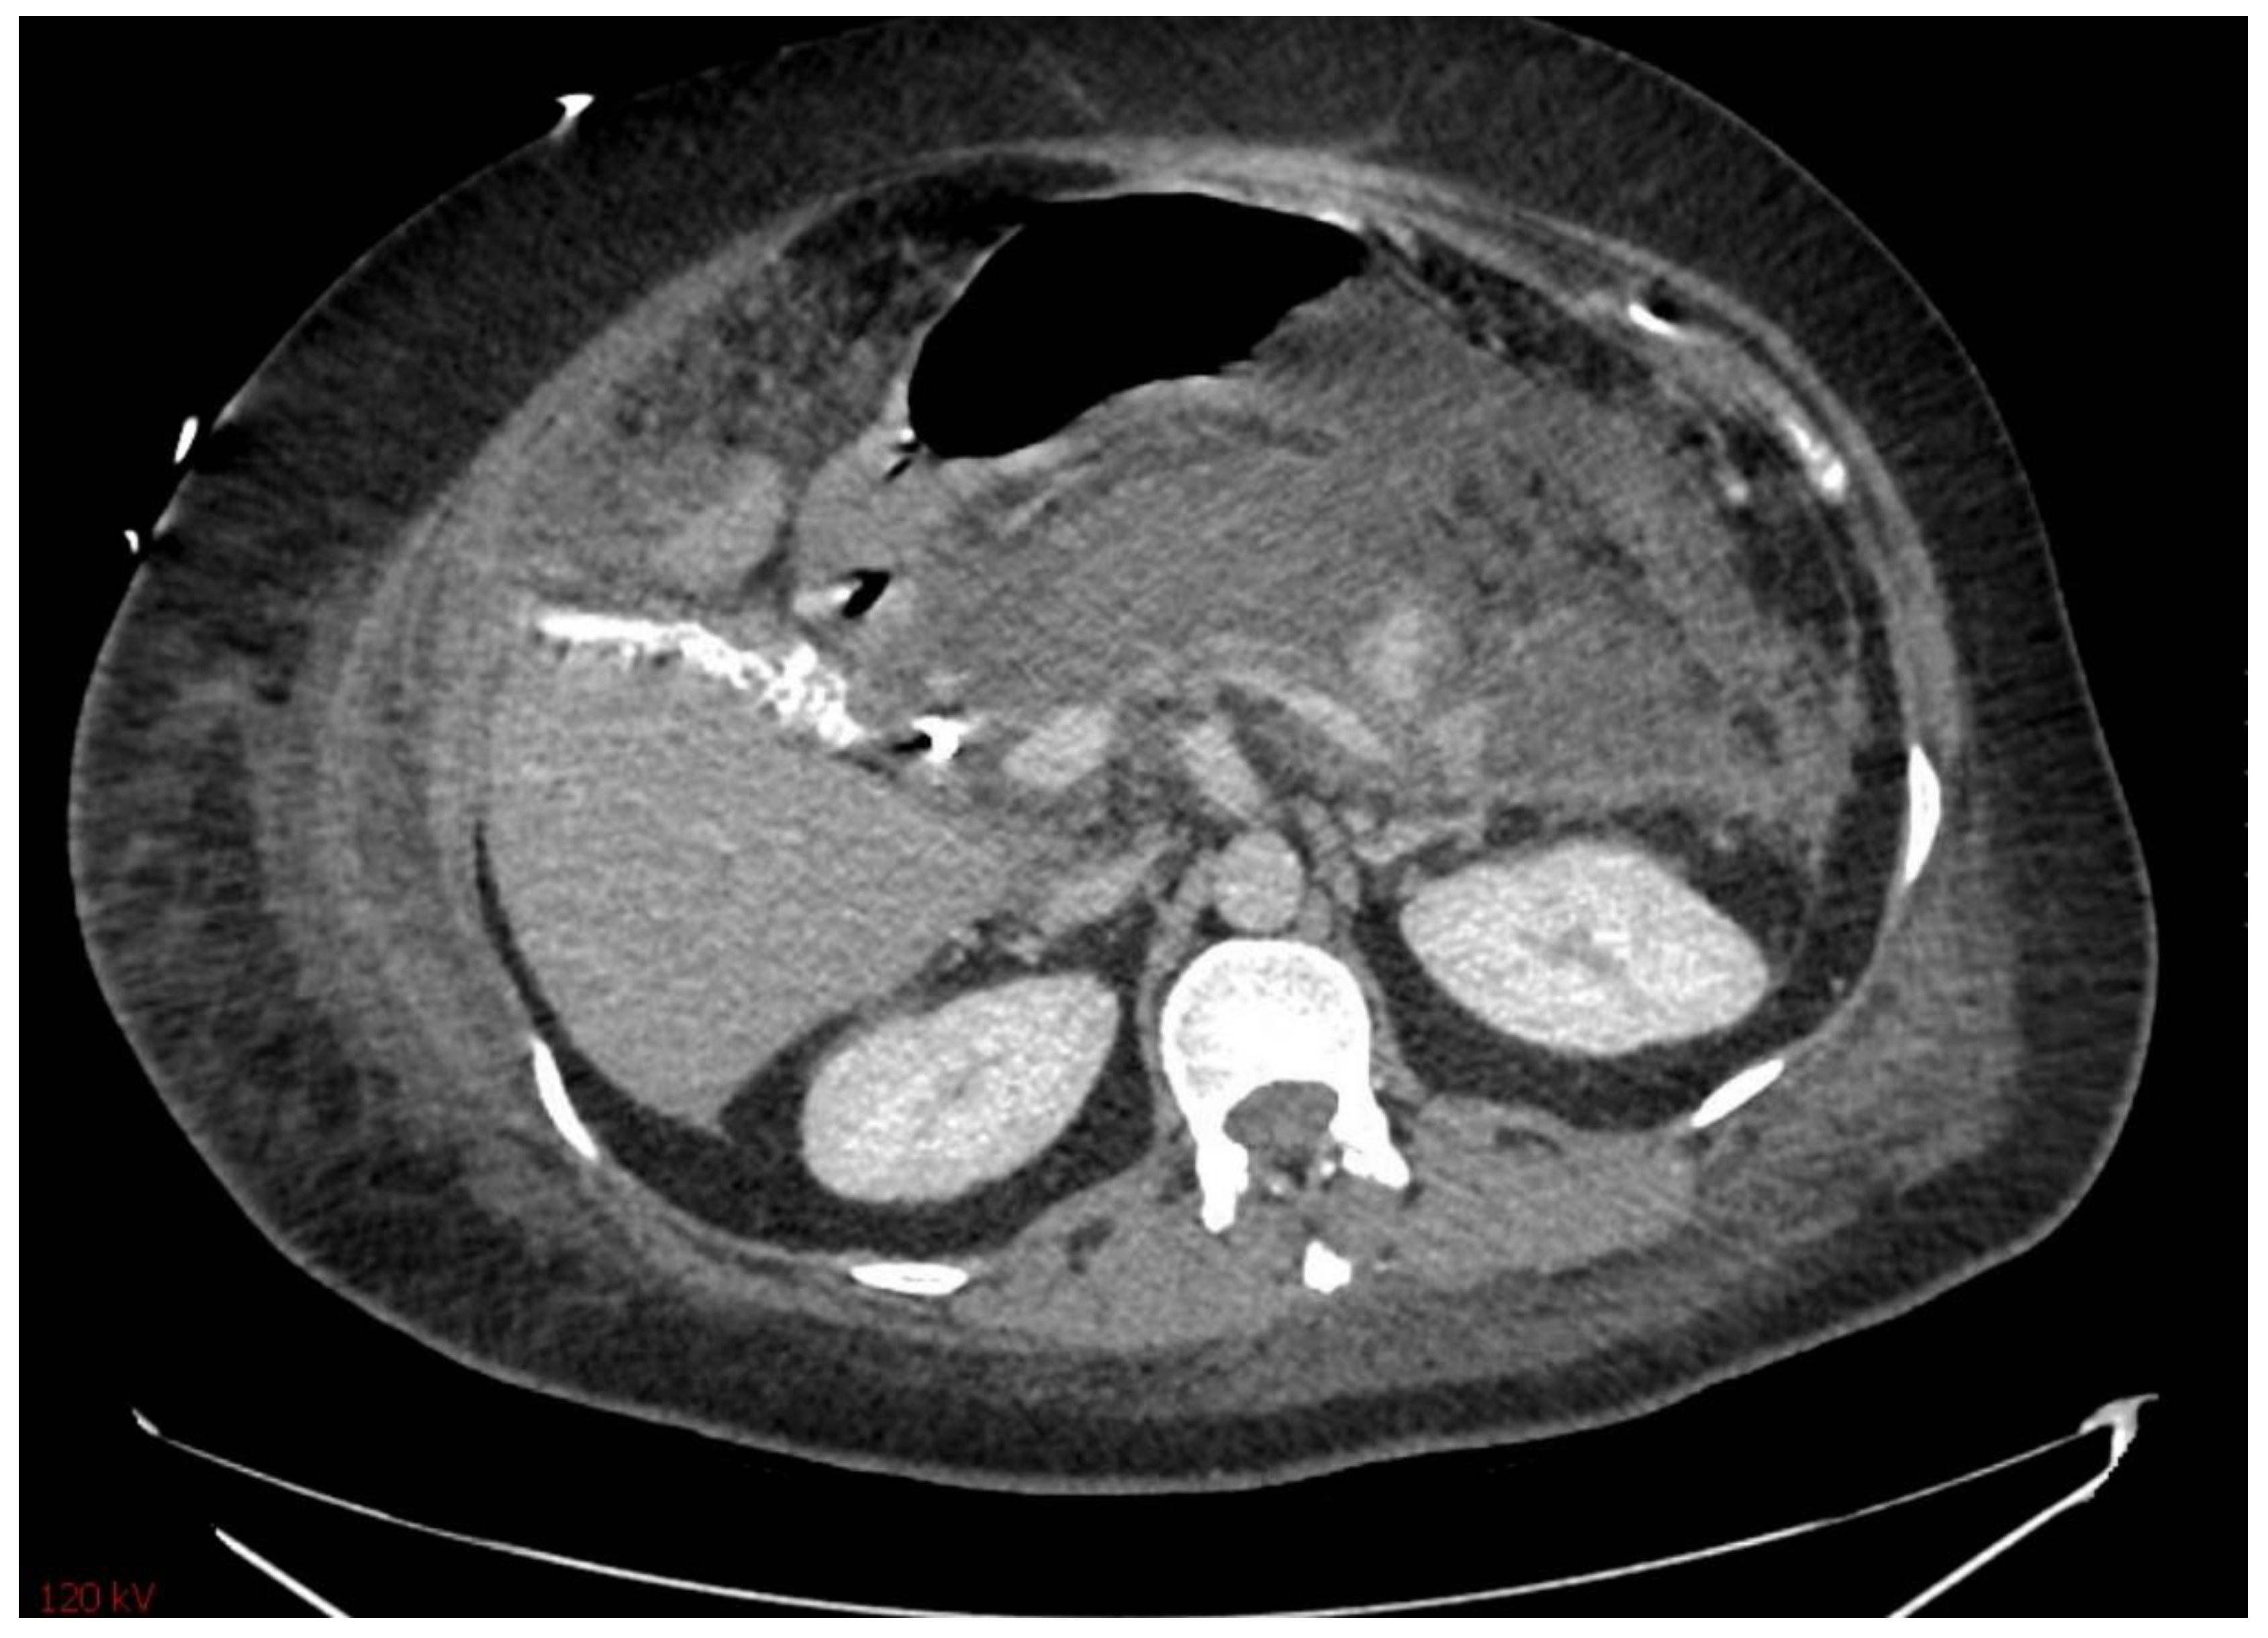

3.2. Severity of Pancreatitis

The prediction of severity is made upon the admission of the patient, but the actual degree of severity is determined once sufficient time has elapsed in order to make a better assessment of acute pancreatitis. The most widely accepted classification of severity is the Revised Atlanta Classification (RAC) [4], which classifies pancreatitis as follows: (1) mild acute pancreatitis with no local inflammation or organ failure, (2) moderately severe acute pancreatitis with transient organ failure (<48 h) or local complications, and (3) severe acute pancreatitis with persistent organ failure (>48 h). In total, 65–70% of patients with acute pancreatitis have an uncomplicated course in which the symptoms resolve within a few days [4,43]. A total of 20–25% of patients develop moderate acute pancreatitis with local pancreatic injury fluid collection or necrosis, leading to prolonged hospitalization. This progression is displayed in Figure 4, Figure 5 and Figure 6. About 10% of patients develop severe acute pancreatitis accompanied by severe pain, a nutritional deficit, and a hospital stay > 4 weeks. These patients require highly intensive critical care with interventions (as indicated) [24].

Figure 6. Pseudocyst of the pancreas.